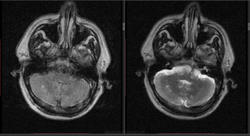

Мужчина 1964 г.р. Жалобы на нарушение памяти, снижение зрения и кратковременную потерю сознания, температура нормальная.

Я думаю что это может быть какой нибудь васкулит, либо Posterior Reversible Encephalopathy Syndrome, о чем можно думать в данном случае?

eto pres

Я представлял синдром с более выраженным изменением сигнала от белого вещества и меньшим - коры.